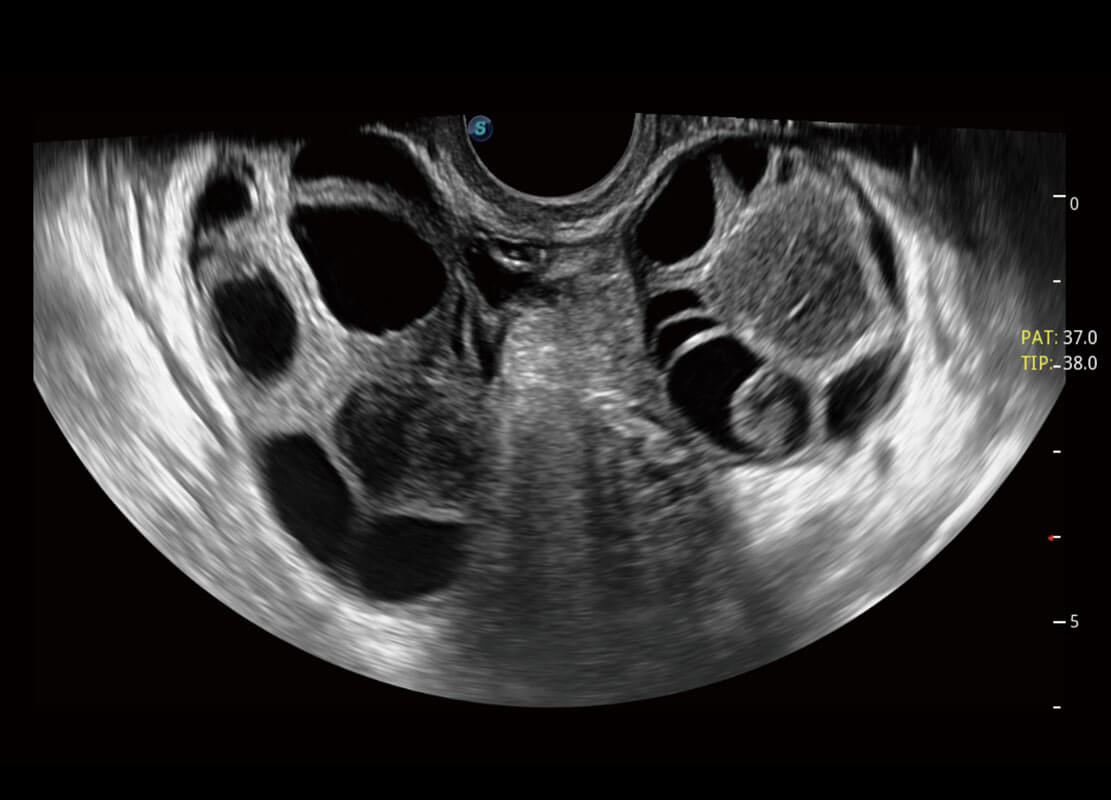

P60优异的图像质量搭载专科探头,在妇科基础疾病的诊断、卵泡生长的监测、输卵管通畅情况的判别等方面为您提供生殖应用方案。

腔内妇科-宫腔分离

腔内妇科-卵巢

腔内三维-宫内节育器

腔内三维-光影成像